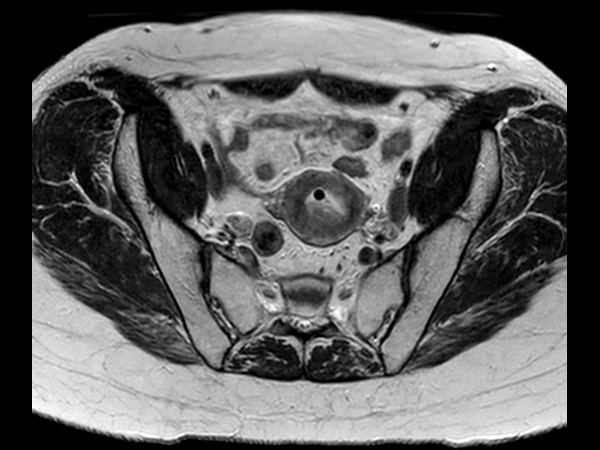

Patient with cervical cancer referred for MR-guided brachytherapy. MR imaging on Ingenia 1.5T with tandem-ring applicator in place for brachytherapy planning.

Axial oblique 2D T2w TSE